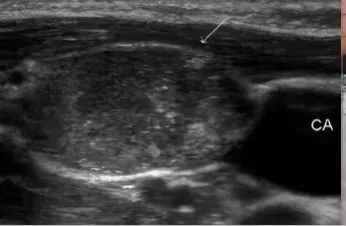

通常结节至少要>1公分以上才能通过临床医生的触诊,可以初步诊断出。随着医学技术的发展,在各种检查手段中,超声机器能更加方便准确地检测出甲状腺结节的大小、形态、位置、血流等情况,更加方便临床医生及患者了解自己结节的情况。

从超声报告中观察,通常甲状腺结节具备几个要素,超声的恶性评分会逐渐增高,从而在结节分级中体现出来。

1、结节内有微钙化;

2、结节与周围甲状腺组织界限不清;

3、纵横比大于1或不规则形的结节;

4、低回声或极低回声;

5、周边及结节內部少量血流信号的“乏血流”改变;